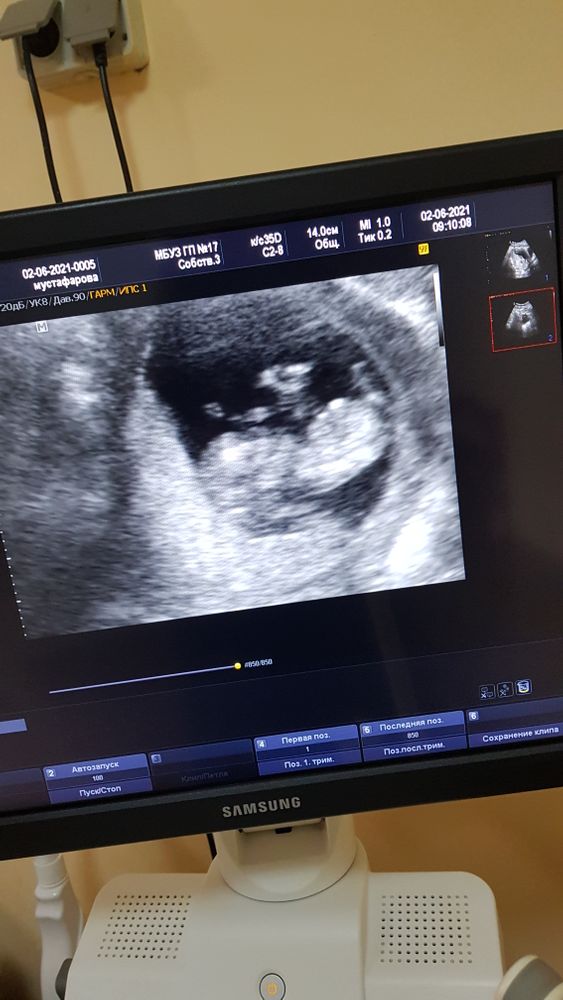

Девочки,привет) 2 июня был первый скрининг. Сказали, что всё хорошо, но единственное голова немного больше,чем должна быть. Теперь переживаю. Через неделю хочу ещё сходить в клинику платно посмотреть. И по срокам не совсем понятно. На 2.06. по последним месячным срок 12,1 по КТР 11.3, а по БПР 13,5. Мне кажется немаленькая разница....

Результаты скрининга и малыша прикладываю.